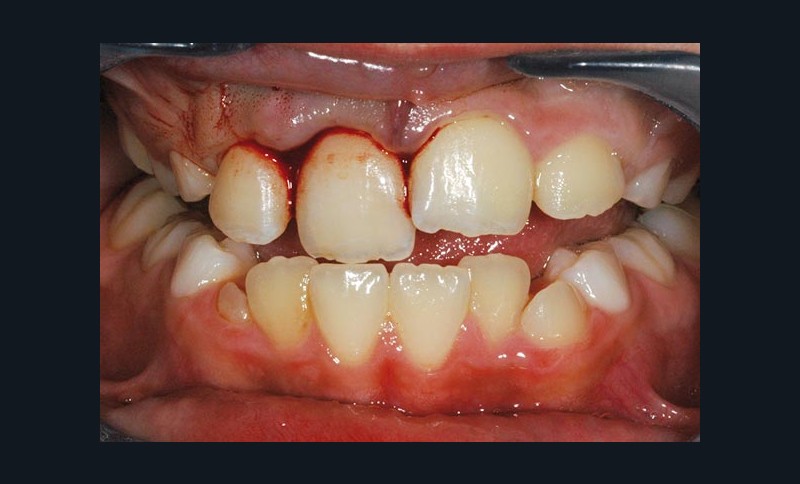

À l’examen clinique, le fragment coronaire peut être mobile, déplacé(fig. 1 et 2) et présenter une dyschromie transitoire de la couronne. Dès lors, un certain nombre de tests complémentaires s’impose.